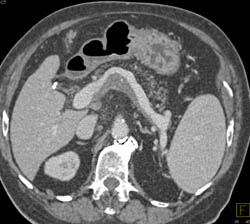

Liver Cyst